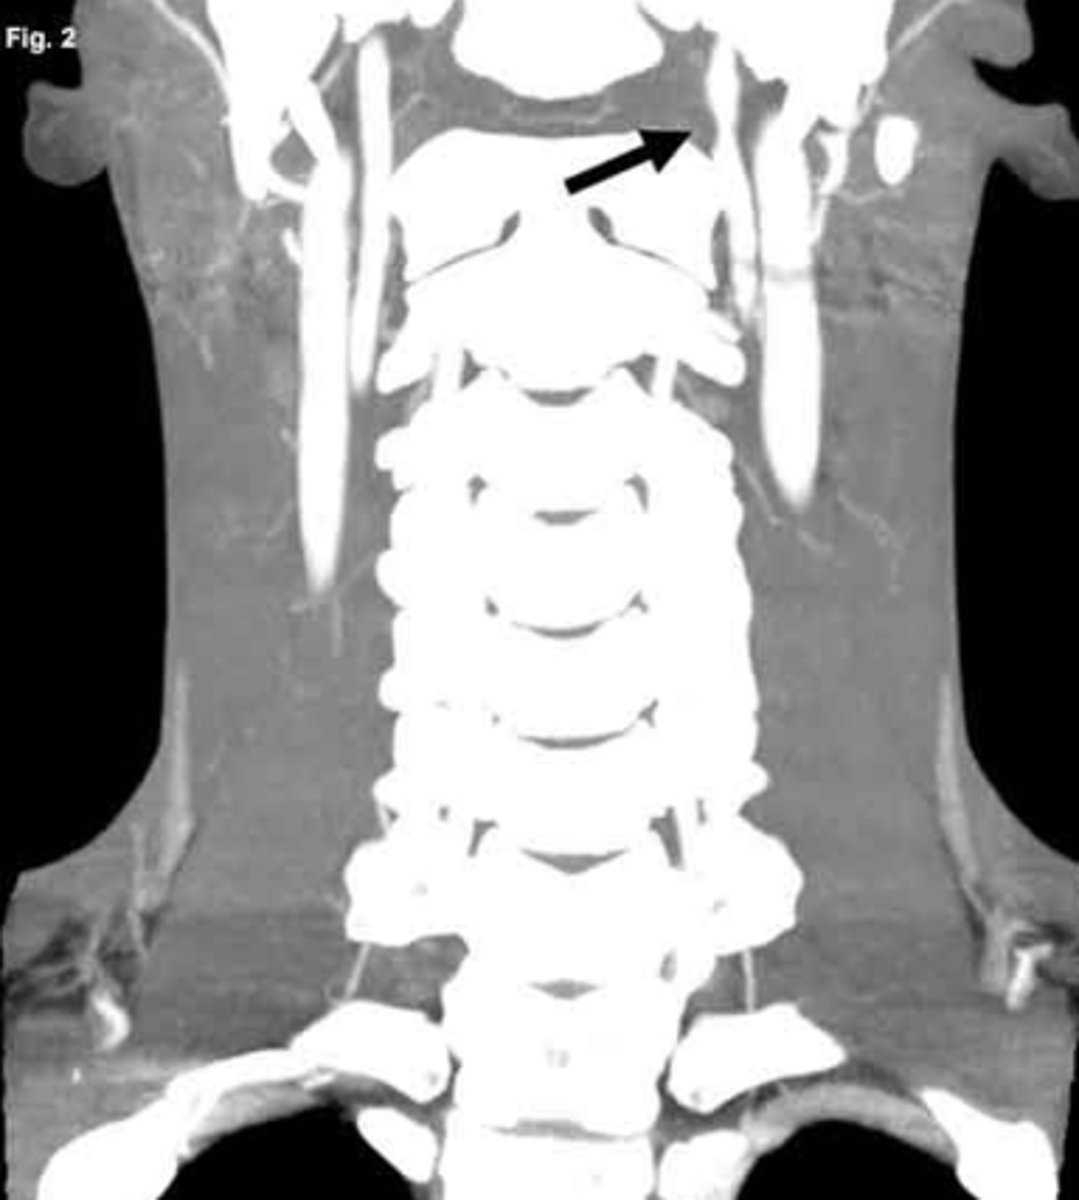

Pancoast tumor that affects the symp fibers traveling over apex of lung

What are some findings of a Pancoast tumor?

Horner's syndrome

chest pain